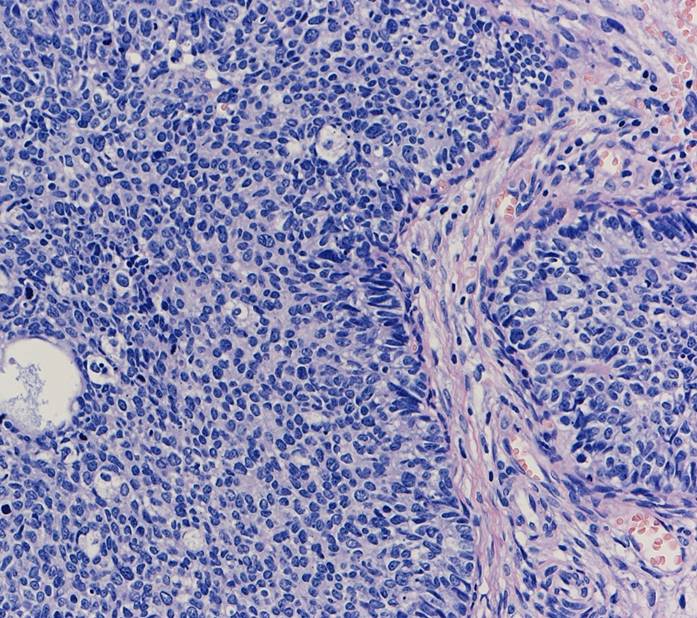

子宮頸部のSCJにおいてクロマチン増量を示す異型上皮が明瞭な

腺管構造や充実性胞巣構造を形成し増生していた。充実性増生を示す成分はN/C比や核分裂像が目立ち、免疫染色ではsynaptophysin、chromogranin A、CD56が陽性であり神経内分泌分化が示唆された。以上の所見より、神経内分泌癌成分を伴う腺癌と診断された。面積的には腺癌成分が8割で神経内分泌癌成分は2割であった。腺癌成分で微小浸潤がみられたが神経内分泌癌成分はin situであった。

腺管構造や充実性胞巣構造を形成し増生していた。充実性増生を示す成分はN/C比や核分裂像が目立ち、免疫染色ではsynaptophysin、chromogranin A、CD56が陽性であり神経内分泌分化が示唆された。以上の所見より、神経内分泌癌成分を伴う腺癌と診断された。面積的には腺癌成分が8割で神経内分泌癌成分は2割であった。腺癌成分で微小浸潤がみられたが神経内分泌癌成分はin situであった。